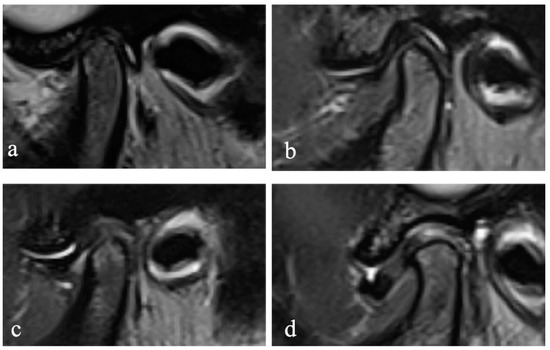

2.3. Assessment of the MR and CBCT Images

The MR images were randomly numbered and evaluated by using Radiant 5.0.0 software (Poznan, Poland) on the same laptop, and the information of the subjects, including the disc position, disc configuration, and JE, were hidden. In the closed and open mouth positions, the maximum section of the articular disc shown on the oblique sagittal PDW image was selected to evaluate the configuration of the disc. According to the method proposed by Raweewan [17], the disc configuration was divided into four types: biconcave, biplanar, convex, and folded (Figure 1). The biplanar, convex, and folded types were defined as deformation. Combined with the oblique sagittal and the oblique coronal PDW images, the position of the disc was described by Tasaki’s method [18]. Furthermore, JE was classified into 0–3 levels (Figure 2) on the oblique sagittal T2W images in the closed mouth position, according to the criteria proposed by Segami et al. [19]. The degree of JE was dichotomized into two groups for intra-group statistical analysis: JE-, grade 0 or 1, and JE+, grade 2 or 3.

Figure 1. Disc configuration. Oblique sagittal proton density MRI showing the classification of disc configuration: (a) biconcave, (b) biplanar, (c) convex, and (d) folded.